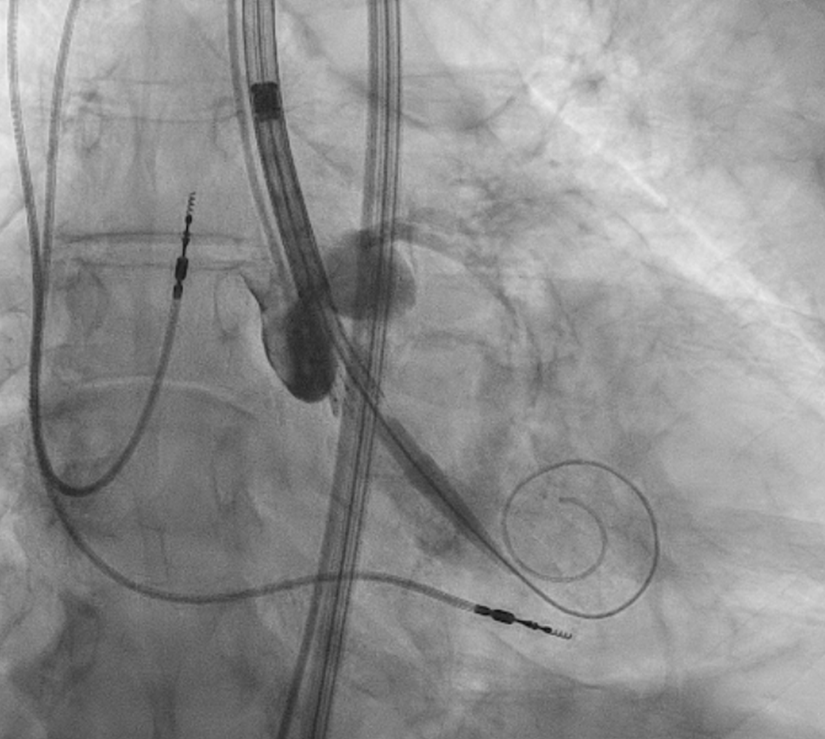

按照标准TF-TAVR流程,术者成功建立血管入路、放置导丝与瓣膜输送系统,在经食管超声心动图(TEE)与血管造影引导下定位瓣膜,启动瓣膜释放程序。

TAVR delivery system positioned across the native valve

TAVR输送系统跨原生瓣膜定位

26 mm Evolut FX valve being deployed

26 mm Evolut FX 瓣膜正在释放